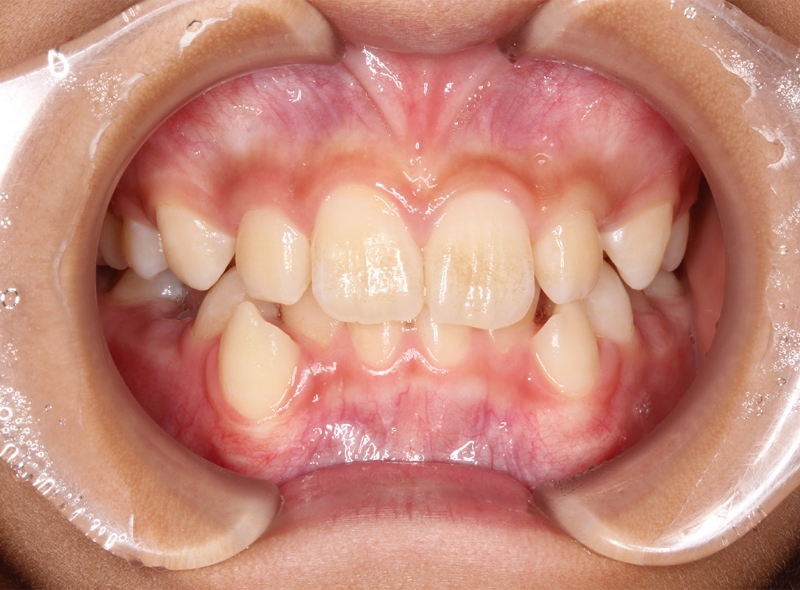

CASE 小児の矯正(出っ歯)

Before

After

| 年齢 | 9歳(治療開始時) |

|---|---|

| 性別 | 女性 |

| 症状 | 上顎前突 |

| 治療法 | マイオブレイス(マウスピース) |

| 費用 | 418,000円(税込み) |

| 通院回数 | 症例による |

| リスク・副作用 | 特になし |

| 備考 | 出っ歯の改善 |